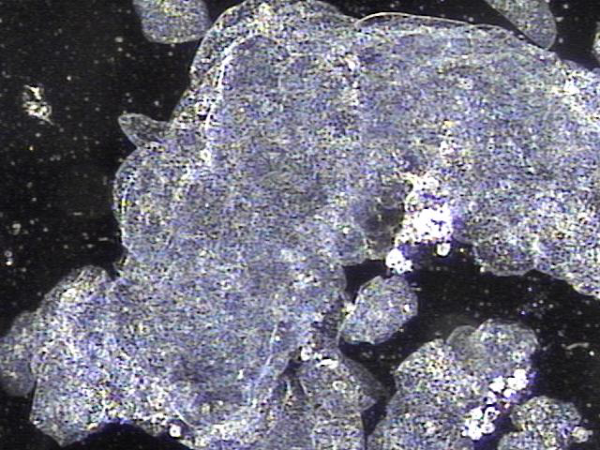

주 2회 전립선과 정낭과 사정관 그리고 정관등의 표적 치료후 치료된 탈락되어 막혀 있던 상피 세포와 프로스타그란딘에 의한 염증 덩어리들의 치료된 현미경학적 사진입니다.

This microscopic image shows the treated area after targeted therapy of the prostate, seminal vesicles, ejaculatory ducts, and vas deferens.

It reveals the removal of old, detached epithelial cells and inflammatory clumps caused by prostaglandins that had been blocking the ducts.

These findings suggest that the blocked passages are now being cleared, helping to restore normal circulation and function.